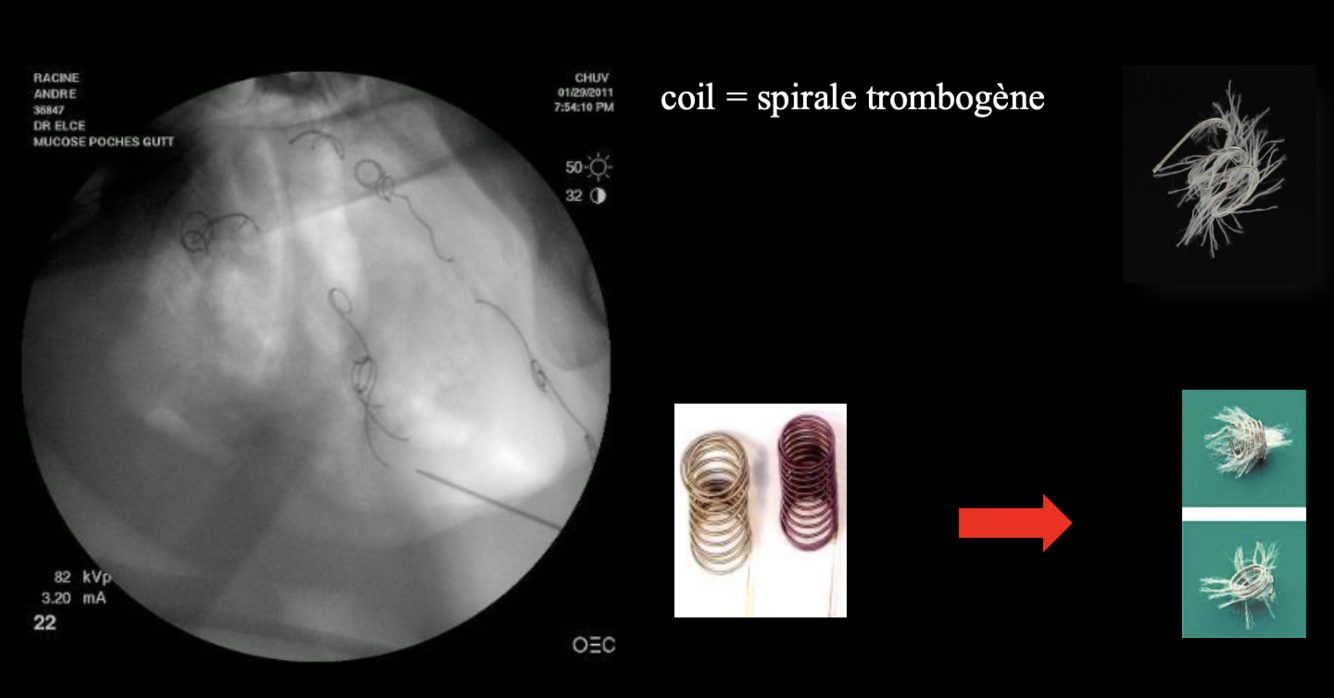

quel est le traitement de la mycose des poches gutturales (5)

2. Embolisation transartérielle (coil

ou plug)

Quelle procédure est considérée comme le “gold standard” pour la mycose des poches gutturales

A

embolisation transartérielle

-> occlusion optimale non invasive

21

Q

V ou F: L’embolisation transartérielle est une procédure non sélective

faux: procédure sélective, on sélectionne l’a. carotide interne, carotide externe ou maxillaire spécifiquement.

22

V ou F: L’embolisation transartérielle est une procédure couteuse, mais qui réussi dans 90-100% des cas

Nommez 2 complications de l’embolisation transartérielle

• possible atteinte de l’artère oculaire (cécité)

• embolie gazeuse